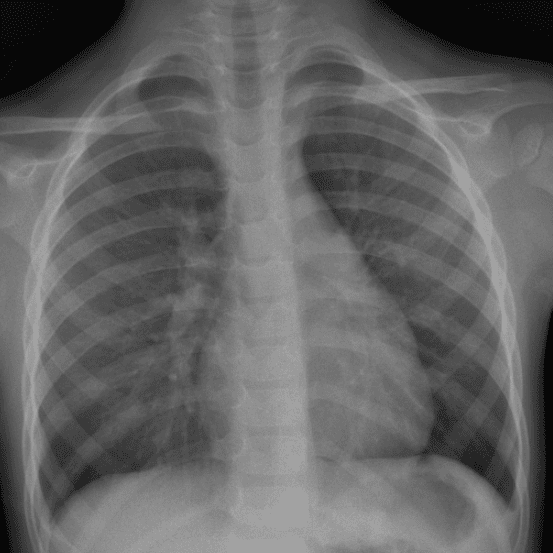

Peds Chest

Practice

Simulates call by including subtle or difficult cases and some normals.

50 cases